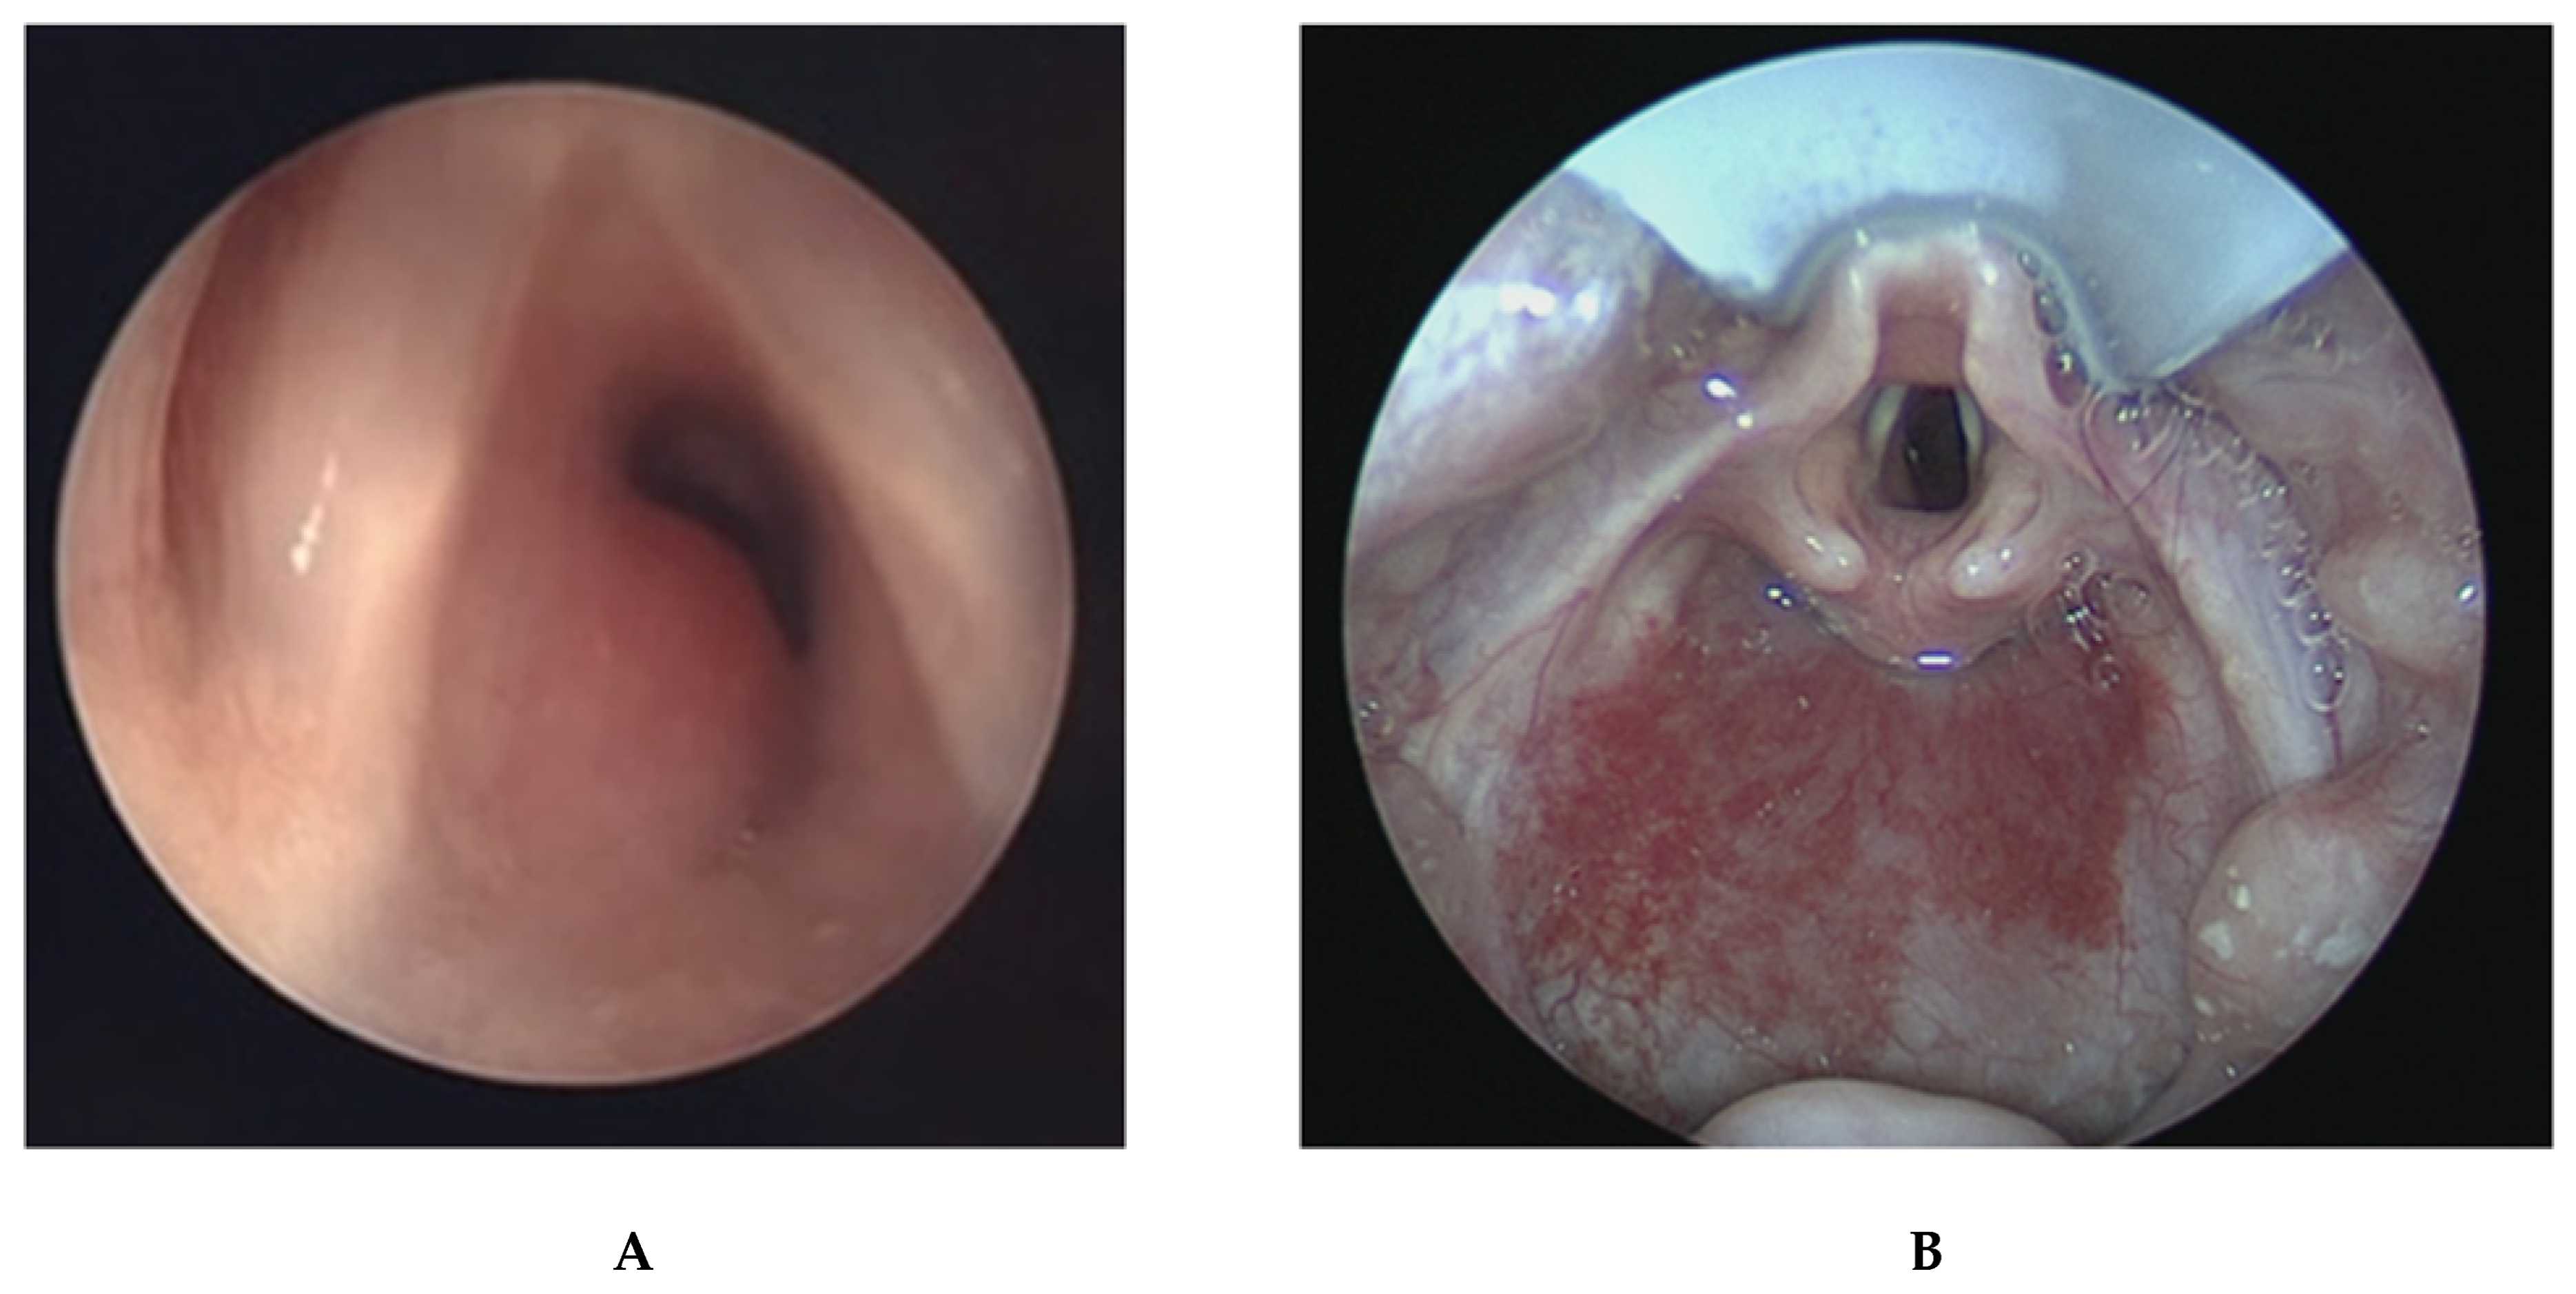

2.4. Laryngeal Webs